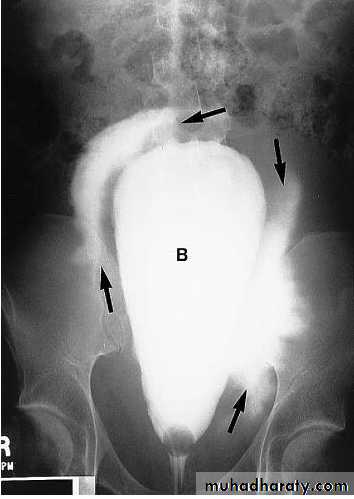

Benign Prostatic Hypertrophy. A radiograph from an excretory urogram shows marked uplifting of the bladder base because of massive enlargement of the prostate (P). The trigone (open arrow) and ureteral orifices (black arrows) are markedly elevated, resulting in a J-shaped appearance to the distal ureters (u). The bladder wall is thickened (between black arrowheads), and the bladder (B) mucosal pattern is prominent.